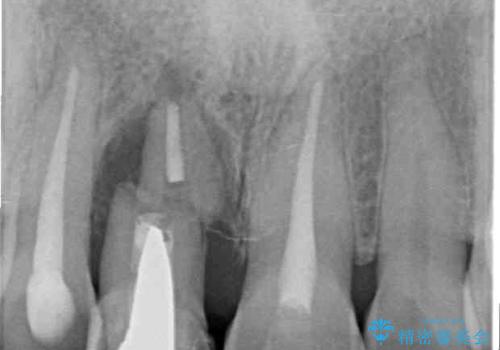

- 仮歯のまま前歯を放置しているとのことで来院された患者様です。

目視で確認できるほどしっかりとした破折が認められ、抜歯が必要と判断されました。

抜歯後は歯肉が痩せてしまうため、歯肉移植を行って歯肉の形態を改善した後、オールセラミックブリッジにて補綴することとしました。